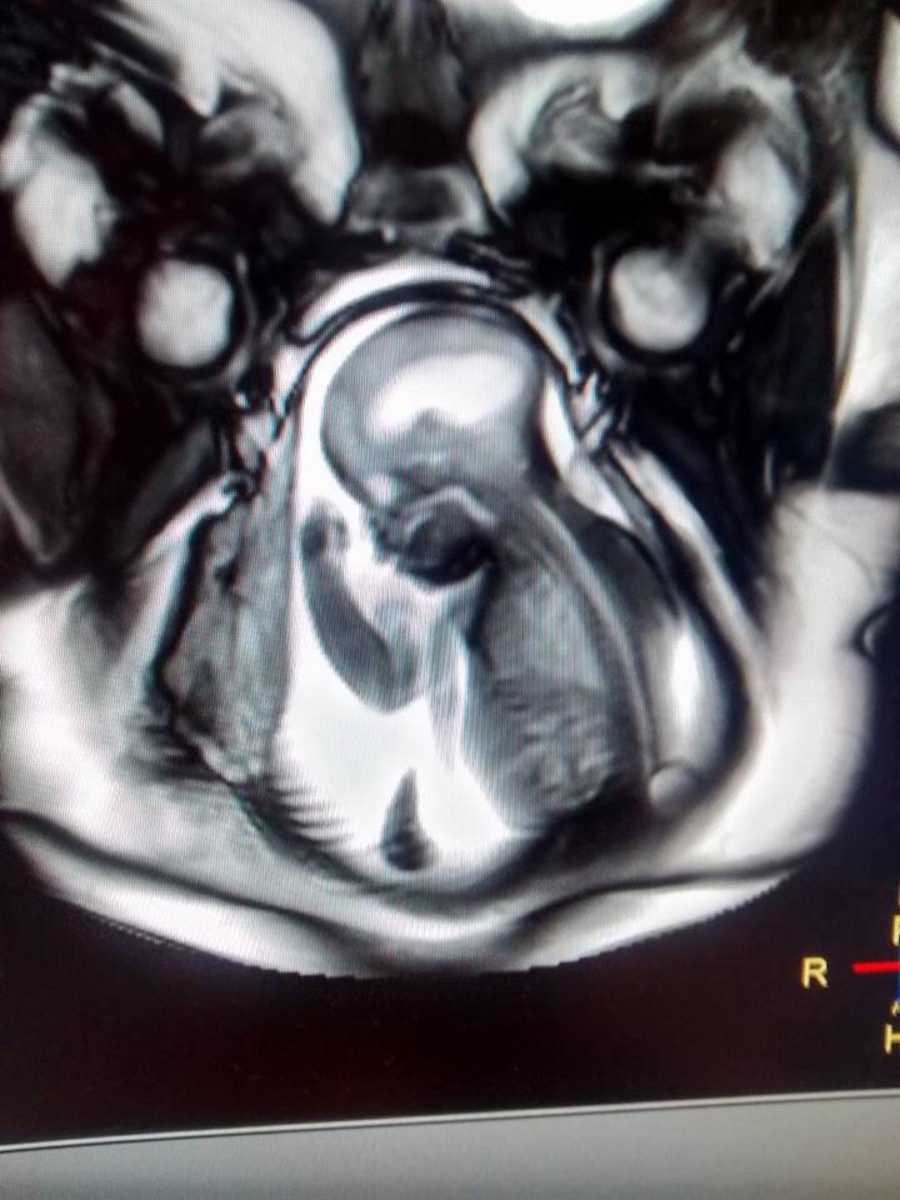

Περάσαμε άλλες 8 βασανιστικές εβδομάδες μέχρι που ο γιατρός μου έκανε εμβρυϊκή μαγνητική τομογραφία. Ο γιατρός μας κάλεσε στο ιατρείο του για να μας κάνει αυτήν την επίσημη και σοβαρή συζήτηση που κάνουν συνήθως οι γιατροί σε αυτές τις περιπτώσεις.

Κανείς δεν το περίμενε όμως ο γιατρός μας ανακοίνωσε ενθουσιασμένος ότι η νόσος Spina bifidaή δισχιδής ράχη όπου έπασχε το έμβρυο, ήταν μία γνωστή νόσος και ο γιατρός ενθουσιασμένος, μας είπε ότι υπάρχουν γνωστές θεραπείες και μεγάλες εξελίξεις στην επιστημονική κοινότητα. Θα ήταν δίπλα μας.